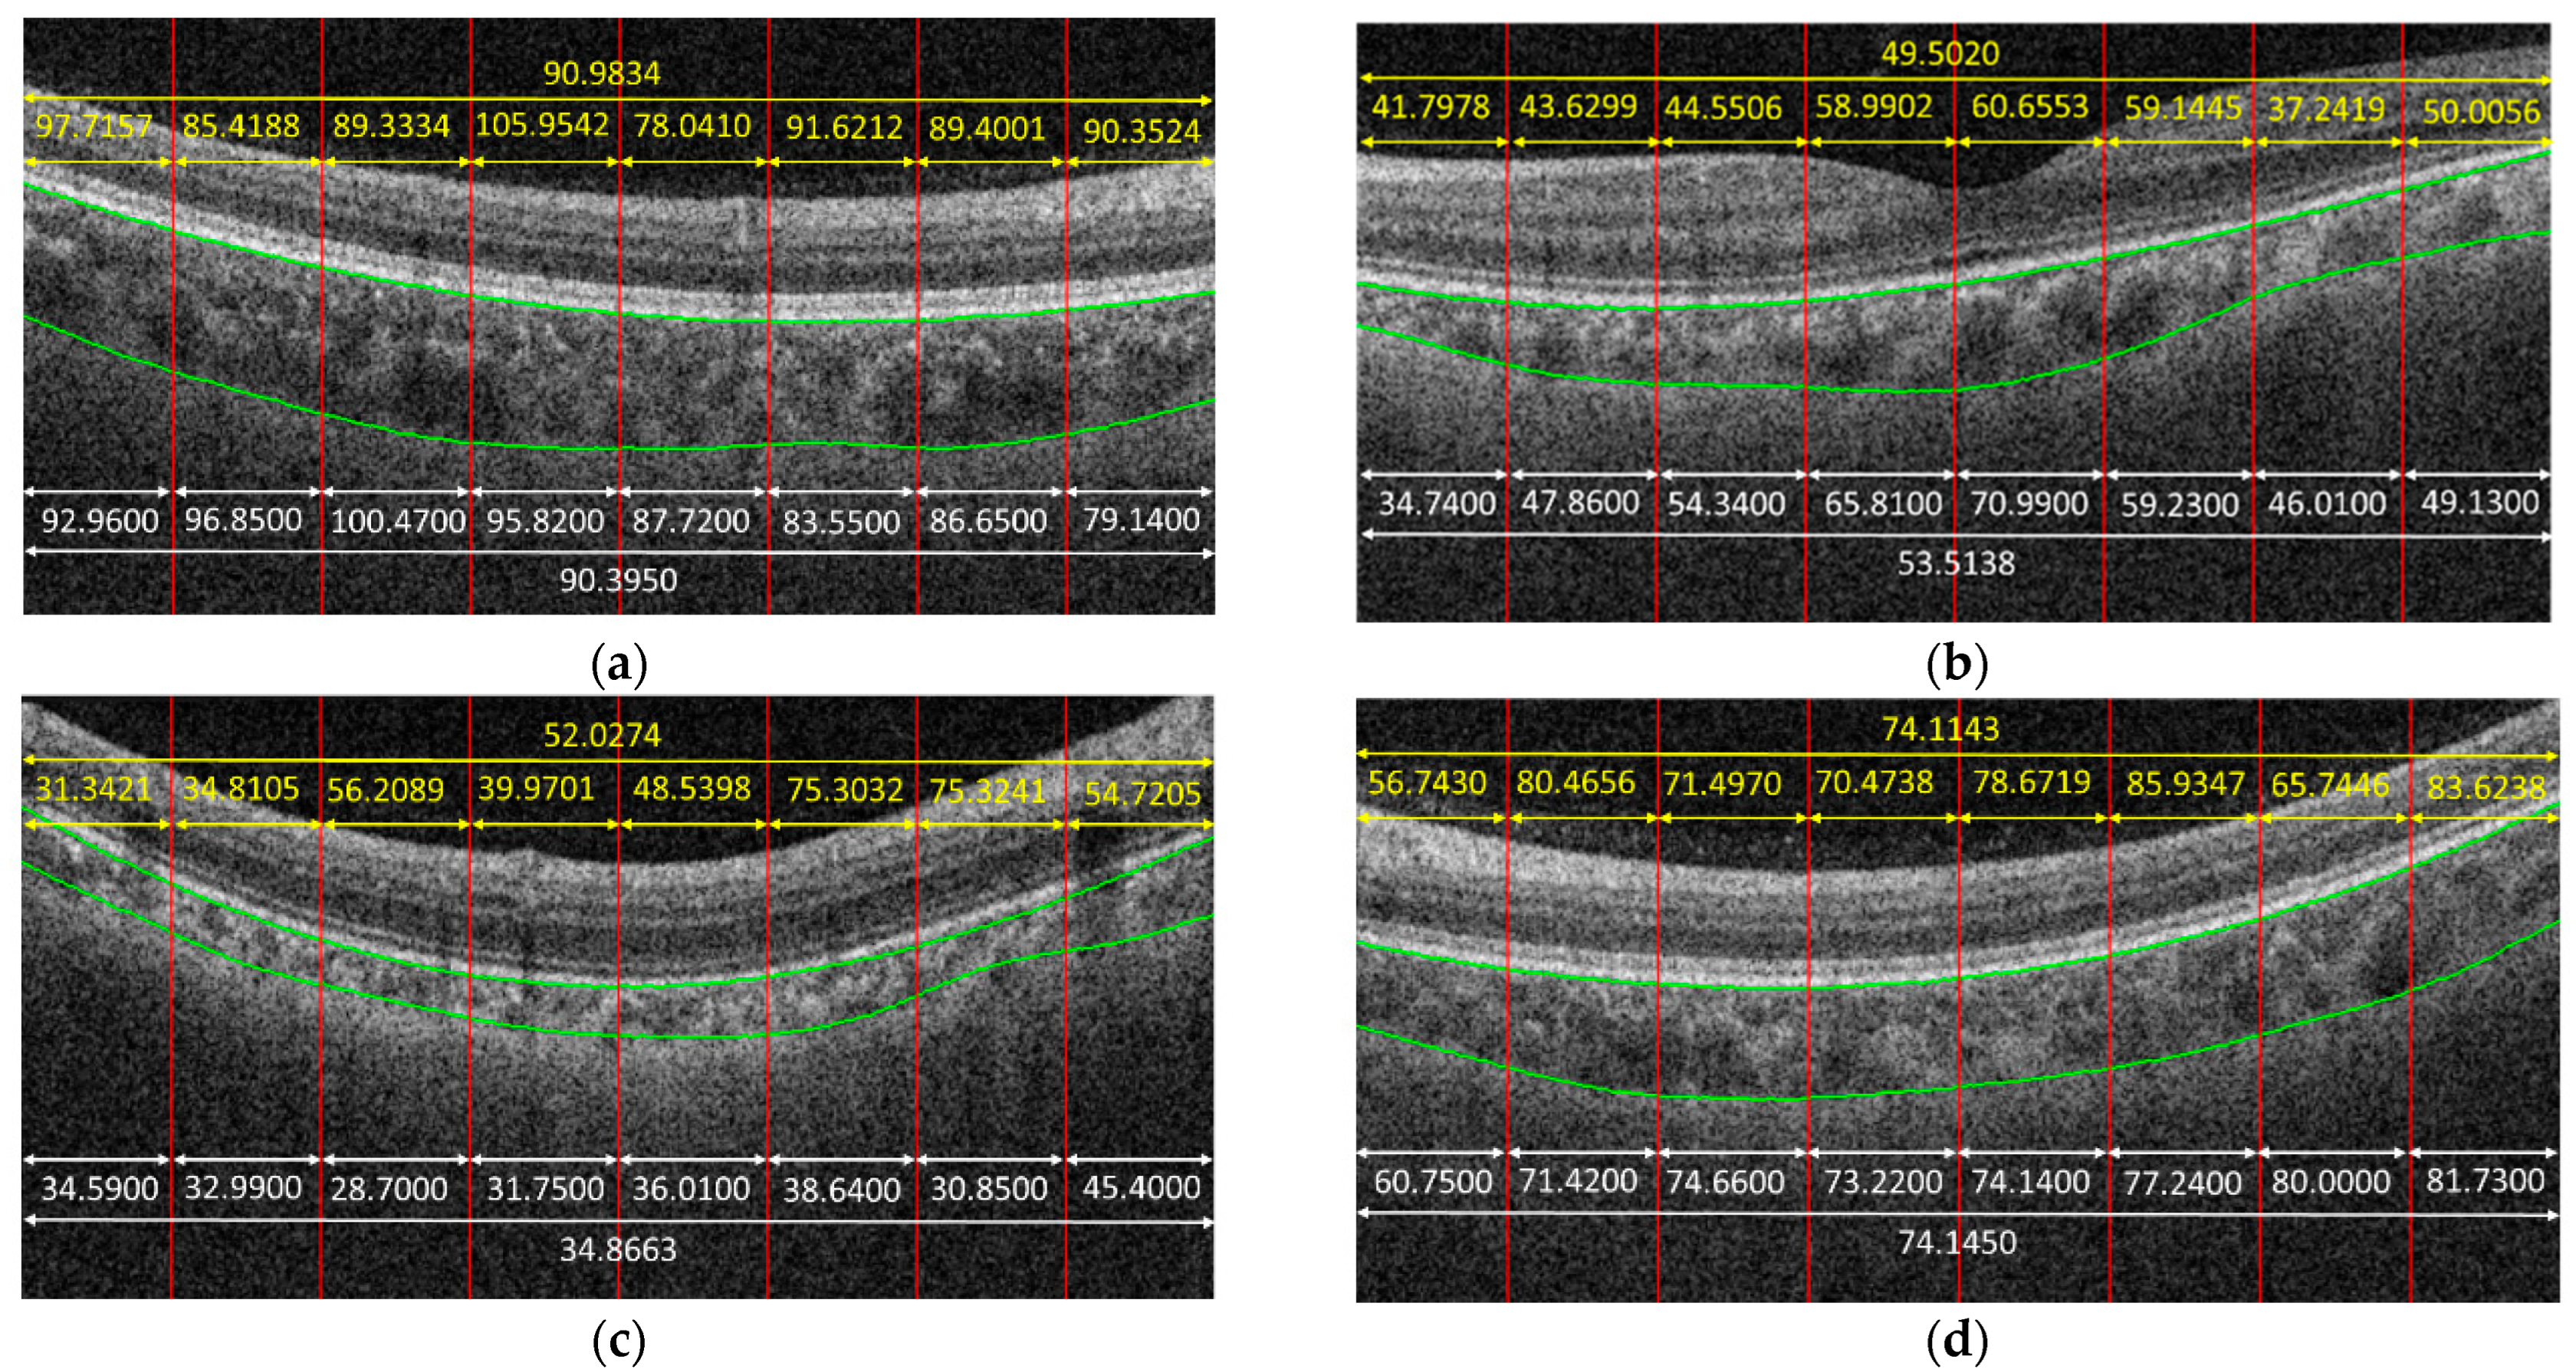

Figure 4 shows some examples to demonstrate the predicted results obtained by the proposed method. In the given examples, eight patches were cropped from a B-scan. The predicted result for each patch is shown in yellow color. The average on the predicted results of each patch cropped from the same B-scan is also in yellow. The white parts in Figure 4 are the corresponding ground truth, and green curves are the boundaries of the choroid. It is observed that the predicted results obtained by the proposed method were very close to the ground truth for some cases, e.g., Figure 4f, while the proposed method might also fail for some other cases, e.g., Figure 4c.

Figure 4.

Examples to demonstrate the predicted results obtained by the proposed method, in which yellow parts are the results obtained by the proposed method. White parts are the ground truth. Green curves are the boundaries of choroid. (a) MAE = 0.5884, (b) MAE = 4.0118, (c) MAE = 17.1611, (d) MAE = 0.0307, (e) MAE = 8.4348, (f) MAE = 0.9919.

From Table 1, we can also observe that the ME value was negative for patches with sizes of 200 × 50, 200 × 100, and 200 × 200, which indicates that the CNNs tended to underestimate the values of choroidal thickness for these cases. While for patches with a size of 400 × 400, the ME value was positive, which means that the CNNs tended to overestimate the values. Another phenomenon observed in Table 1 is that the performance at the B-scan level was always better than the performance at the patch level regardless of the patch size. The reason is that the mean thickness of choroid in a B-scan is computed by taking the average of the thicknesses on the patches cropped from that B-scan, which makes the errors in patch level offset each other to some extent. Figure 4d gives an example; as can be observed, the trained CNN model could not predict the choroidal thickness correctly for some patches—namely, the predicted results were larger or smaller, compared with the ground truth. However, when we took the average, the biases in larger and smaller cases offset each other; thus, the precision of choroidal thickness at the B-scan level improved, compared with that at the patch level.